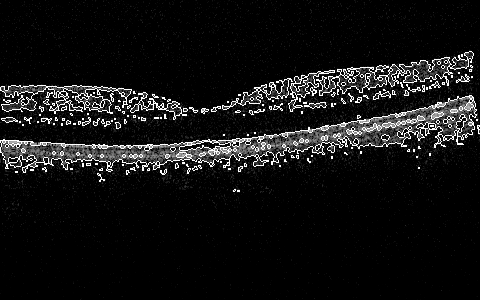

Sun et al. covered various aspects of the OCT image processing and classification using earth mover distance, SVMs, providing for detection of the nacre’s layer thickness and other works, e.g. Sun and Lei (2009, 2010). The most recent work in a 3D algorithm for segmentation (submitted) is by Sun and Zhang that explores position determination for ILM, RPE, and IS/OS in a 3D volume in an efficient and robust manner by determining intensity change on both sides of the boundary simultaneously and then smoothen the recovered surface using 3D intensity difference Sun and Zhang (2012). Some segmentation results are shown in Figure 1, and more are within the cited work.

More interesting preliminary results include global 2D (2D at the moment, per slice, but will expand the window to 3D space next) processing that includes in one algorithm some subalgorithms that do preprocessing, skeletonizing, or filling/thinning, and active-contouring of the images from the Zhang-Suen transform. There are many of the options and configurable parameters to try, but already now the outlines of the ILM, IS/OS, RPE can be seen in a very draft debug mode in Figure 7, Figure 8, Figure 5, Figure 6, Figure 9, and Figure 10.